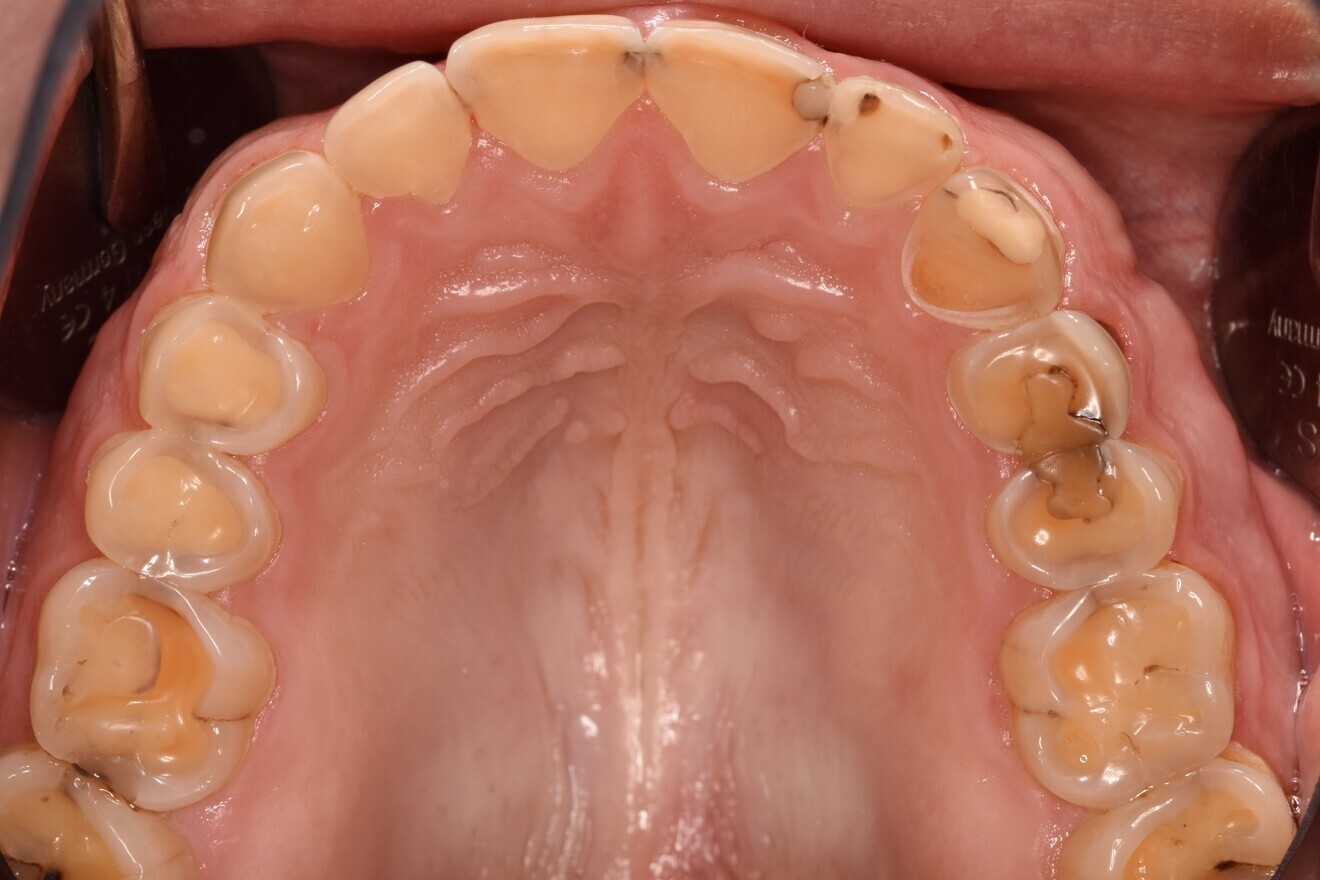

Fig. 1d: Almost complete loss of the occlusal relief in the upper jaw.